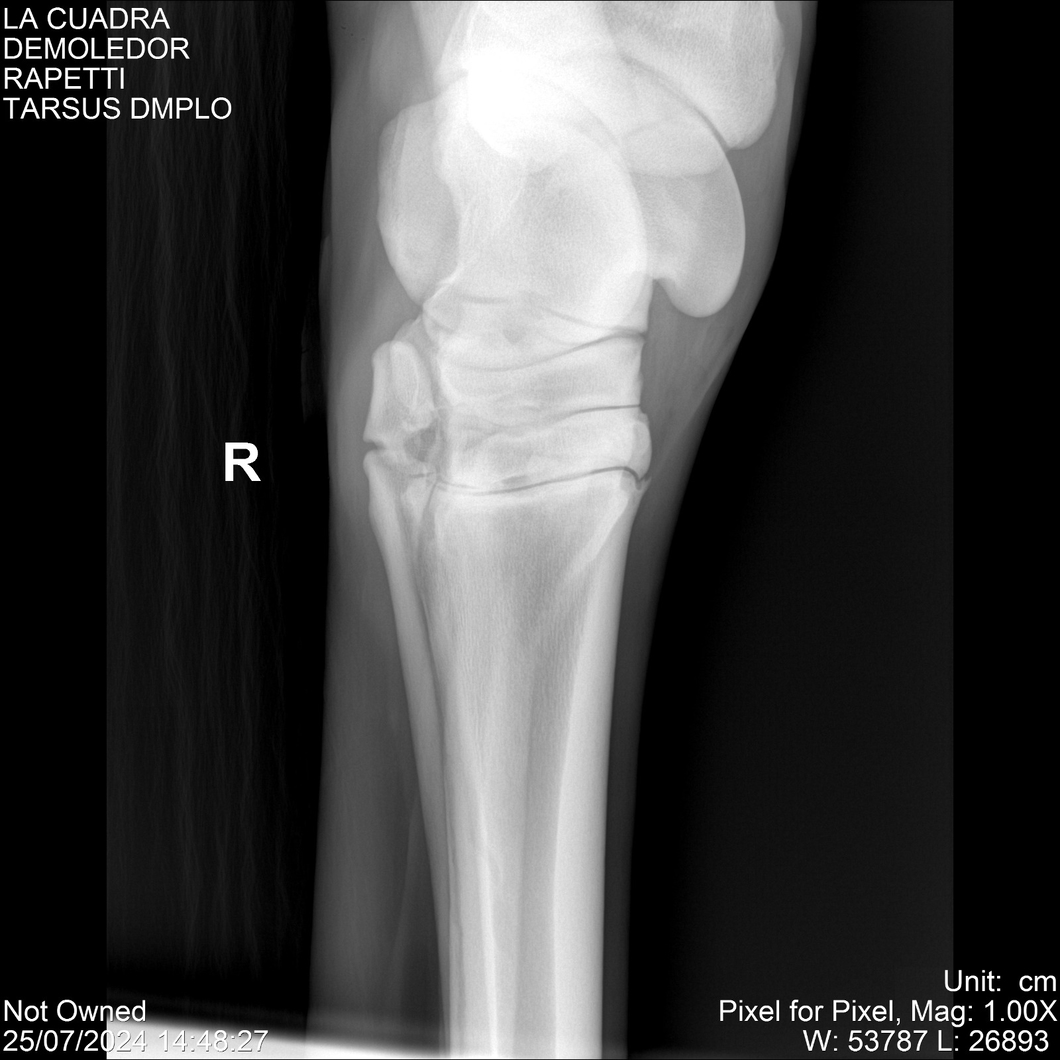

LOTE 14, DEMOLEDOR 🔥 🔥 🔥 Lote Anterior Volver al remate Lote Siguiente Ficha Contacto Montevideo - Ficha del Lote Identificador: #284454 Categoría: Yeguarizos Montevideo - 89 Visualizaciones ClicData Contacto Empresa: Abelenda N. R., Walter Hugo Nombre*: Teléfono* : E-mail* : Mensaje Enviar Registrese gratis Este contenido Exclusivo está disponible sólo para usuarios registrados Ingresar